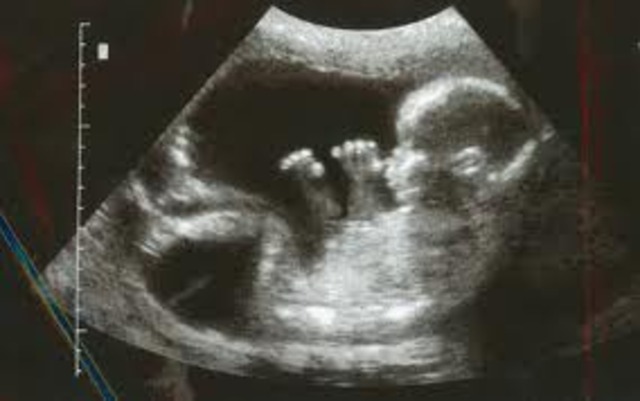

Mom: Abdomen is still growing, most of the sickness is gone, appetite is increasing.

Baby: About 3 inches. The baby can suck its thumb, swallow, hiccup, and move around.Facial features are becoming more clear.